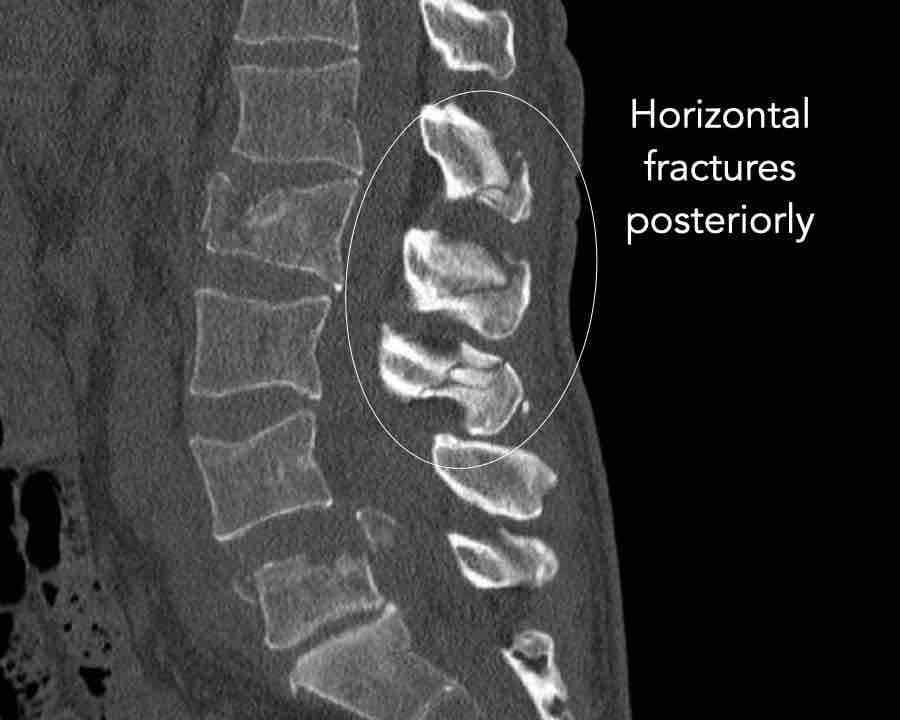

Findings

- No dislocation ( no C type).

- Mainly horizontal fractures of spinous processus at multiple levels (B-type).

- Split fracture L2 (type A2).

Conclusion

Injury type B2 + A2 at level L2.